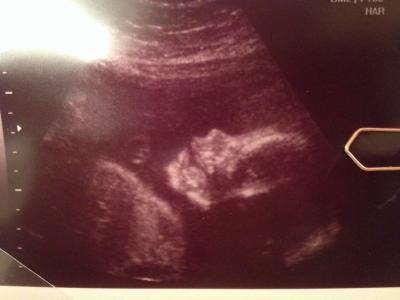

Guten Morgen meine Lieben, Gestern Abend hatte ich wieder Vorsorge! Also als erstes es ist alles prima Bin jetzt bei 81 kg aber seit Anfang sind das nur 5 kg und das ist super...aber hatte ja auch ordentlich Reserven Dann haben wir gleich noch den kleinen zuckertest gemacht und meine Werte waren alle prima auch der Eisenwert! Also kann alles so bleiben! Dann durfte ich zwischendurch auch noch zum Baby-TV. Hab ein tolles Bild bekommen aber 3D hat wieder nicht funktioniert weil Krümel mit der Plazenta gekuschelt hat! Liegt auch schon richtig rum mim Kopf nach unten...drum hab ich auch immer wieder einen leichten Druck nach unten! Wiegen tut der kleine Mann ca. 670-700g! So, nun das etwas schlechtere...dadurch das er schon so schön nach unten liegt wird das mit meinem Rücken und dem Ischiasnerv wohl nicht mehr besser...bin jetzt bis nächste Woche erstmal wieder krankgeschrieben und dann hab ich Urlaub und dann wird weiter gesehen! So, war jetzt doch etwas länger...

Bild zu Gestern FA-Termin - Forum für April - Mamis

Auch wenn kein 3D Bild, das Bild ist zuckersüss!!!! Das mit dem Rücken ist natürlich blöde, aber die kleinen haben doch noch genug Platz um sich zu drehen. Wer weiss also ob er sich nicht doch noch mal dreht und es dann bei dir doch wieder besser wird?!